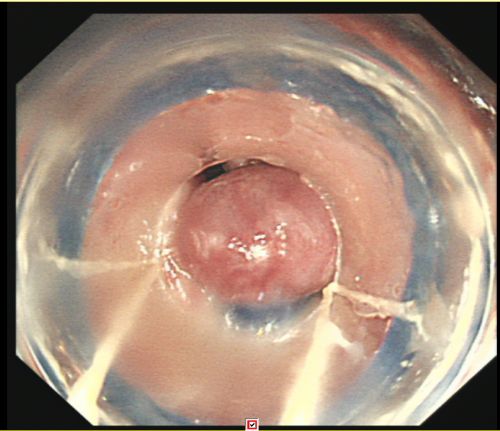

省医岳麓山院区综合内科彭娅主任团队为患者施行胃镜下食管曲张静脉套扎及硬化剂注射治疗。

由于血管压力高,手术风险大,术中发生大出血、窒息及异位栓塞的风险非常高。综合内科主任彭娅反复与家属沟通取得理解配合后,为易某实施改良后内镜下止血技术——食管曲张静脉套扎+硬化剂注射治疗。所幸手术过程顺利,术后继续予以降门脉压力、护胃、减轻腹水、维持内环境稳定等对症支持治疗。经过积极治疗,患者病情趋于稳定,已恢复饮食,精神状况好转,于215日出院。